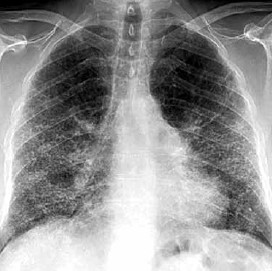

Mulher de 63 anos de idade apresenta quadro de tosse progressiva e dispneia. Ela nega qualquer história de artrite, lesões cutâneas ou queixas oculares. Não há tabagismo ou exposição ocupacional. Ao exame físico: queda do estado geral; afebril; pulso: 90 bpm; frequência respiratória: 32/min; pressão arterial: 119 x 76 mmHg; baqueteamento digital; ausculta pulmonar com crepitações bilaterais (tipo “velcro”). Gasometria arterial em ar ambiente: pH 7,47; PCO2: 32 mmHg; PO2: 60 mmHg. Há queda da saturação arterial de oxigênio ao esforço leve. A pesquisa de tuberculose no escarro é negativa. A radiografia de tórax é mostrada abaixo.

(Arquivo pessoal; imagem usada com autorização)

Nessa paciente, o diagnóstico mais provável é